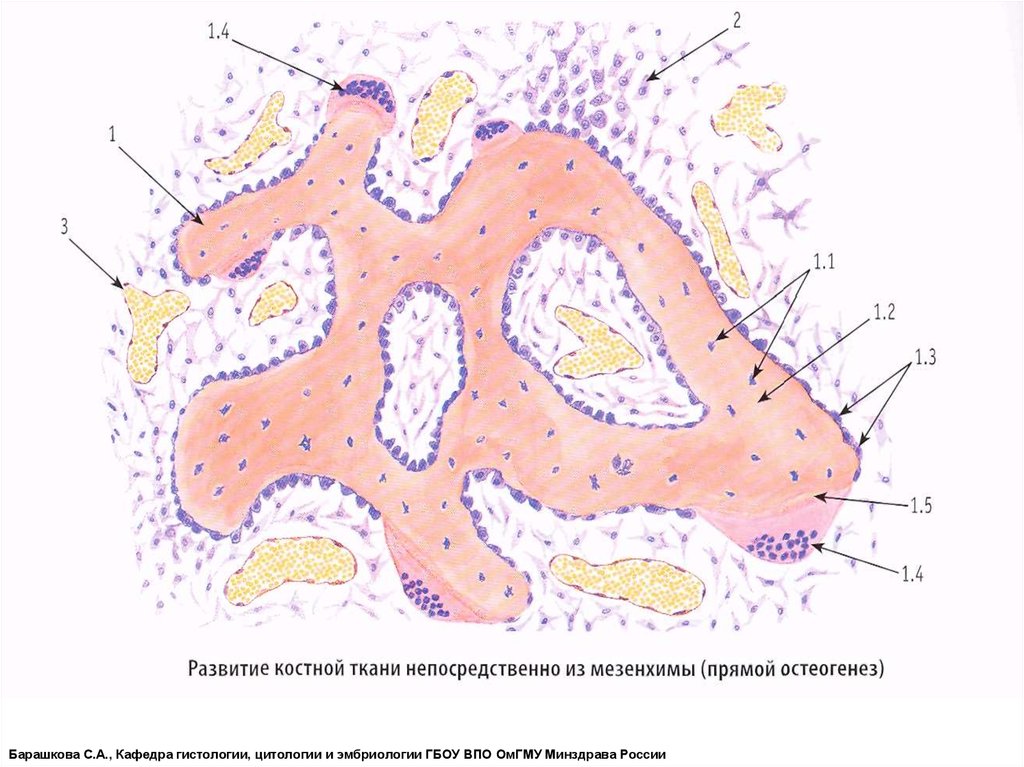

Структура грубоволокнистой костной ткани: наглядные примеры